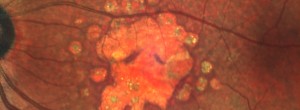

KODIAK: Estudio fase II en pacientes con DMAE forma exudativa.

Ensayo clínico TALON: Eficacia y seguridad de brolacizumab en el tratamiento de la DMAE exudativa

Ensayo clínico LUCERNE: Eficacia y seguridad de FARICIMAB respecto de aflibercept en el tratamiento de la degeneración macular asociada a la edad exudativa

VELODROME: eficacia, seguridad y farmacocinética de ranibizumab 100 mg/ml a través de un PDS en pacientes con nDMAE